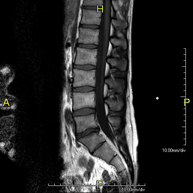

Prueba diagnóstica no invasiva que consiste en la obtención de imágenes de alta definición anatómica de la lumbar y sacra, mediante el empleo de un campo electromagnético y ondas de radio (con un emisor y un receptor). No utiliza radiación ionizante. Indicaciones: traumatismos, ciática, hernias discales, tumores, infecciones. - RM Mielografía

Prueba diagnóstica no invasiva que consiste en la obtención de imágenes de alta definición anatómica de la lumbar y sacra mediante el empleo de un campo electromagnético y ondas de radio (con un emisor y un receptor). No utiliza radiación ionizante. Indicaciones: traumatismos, ciática, hernias discales, tumores, infecciones. - RM Sacro-cóccix